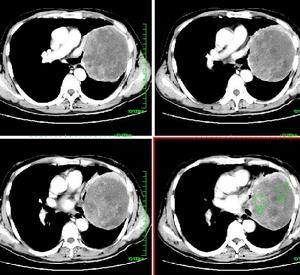

2.影像學檢查頭顱CT、MRI早期無異常改變,病情進展期可見普遍性腦萎縮,腦池寬、腦回小和腦室擴大,多數(80%)無局灶性改變。發現少數病例MRI可見雙側底節、丘腦後部長T2信號。有時較不明顯,如用質子像、Flair和彌散MRI可見明顯增強信號。具有診斷意義。